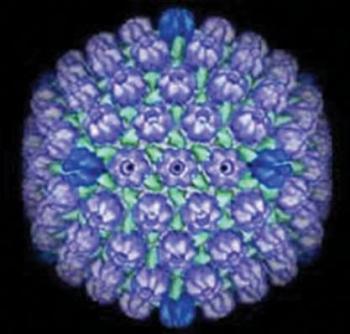

A herpes simplex vírus (HSV) egy közepes nagyságú DNS-vírus, melynek két fő, fajspecifikusan fertőző típusát ismerjük, de több enyhén módosult átmeneti formája is van. A HSV1 betegséget okoz a szájnyálkahártyán, a garatban és a bőrön. Elemi jelensége a vesicula. A HSV2 elsősorban a genitaliákat fertőzi, de orális betegségben is kimutatták. A HSV mindkét formája azonos léziót produkál, de hosszú távon a HSV2 szerepelhet a cervix carcinomák kialakulásában (ezt eddig csak szövettenyészetben igazolták, HSV2 hatására emelkedett a proliferációs ráta). A száj és arc léziókban elsősorban a HSV1 szerepel.

6.1. ábra. A HSV elektronmikroszkópos képe